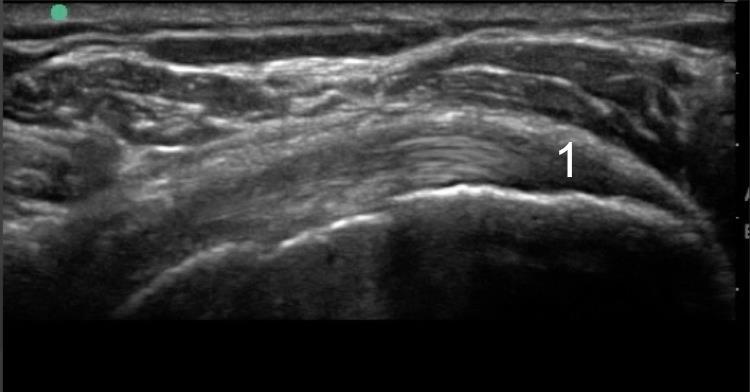

1. Tendon Insertion: not tendinosis

This is a normal tendon showing the expected anisotropic insertion.